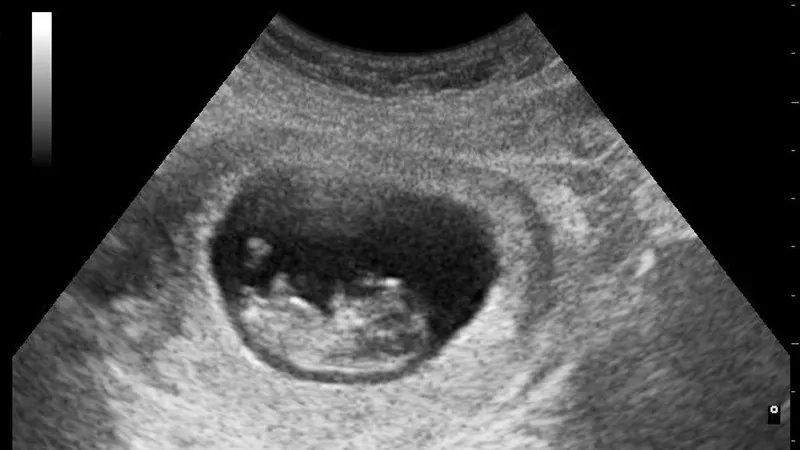

Een zwangerschap beëindigen mag in Nederland in de meeste gevallen van de wet tot 24 weken. In de praktijk wordt doorgaans 22 weken aangehouden, omdat de duur van de zwangerschap niet zo nauwkeurig te bepalen is. Na de wettelijke termijn mag het alleen als er zwaarwegende medische redenen zijn, bijvoorbeeld als het kind niet levensvatbaar is.